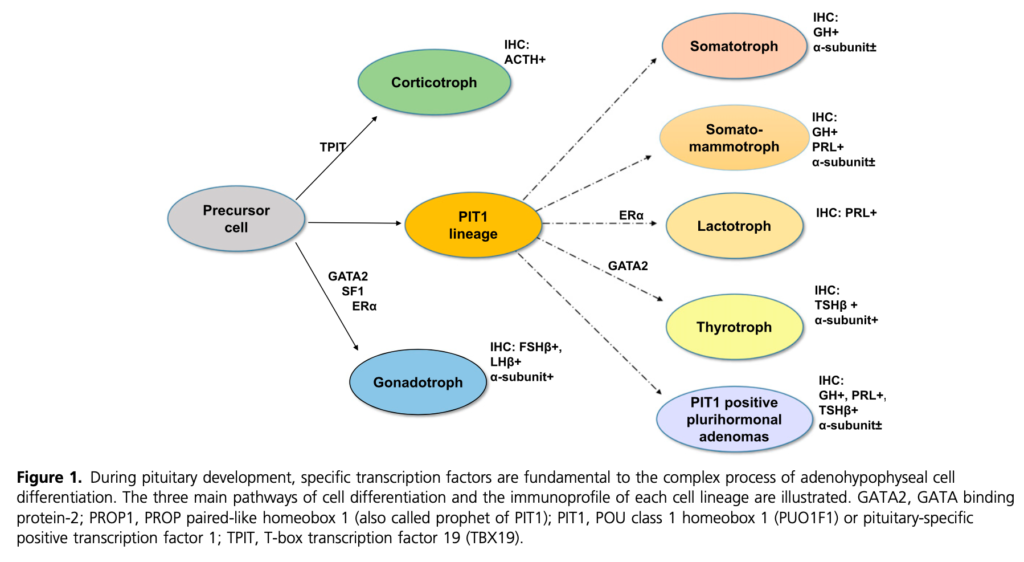

下垂体前葉細胞の発生

TPIT(Corticotroph)、SF1(Gonadotroph)、PIT-1(Somatotroph、Lactotroph、Thyrotroph)。

*このような発生過程があるのでPRLを同時産生するGH産生腺腫(先端巨大症)は少なくない。